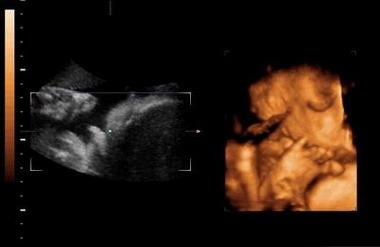

四维报告单子上的名词都有哪些意思?

枕额径(OFD):胎儿鼻根至枕骨隆突的距离,又称前后径,也是计算胎儿头从前到后最长的部分,以这个数据来判断胎儿发育情况和孕周。

头围(HC):环头一周的长度,也叫胎头周长,是计测头的一周地长度的数值。用于确认胎儿的发育状态。

腹围(AC):肚子一周的长度,也叫腹部周长,是计测胎儿肚子的一周的长度。用于和APTD(躯干前后径)和TTD(躯干横径)一起来推测胎儿的发育。